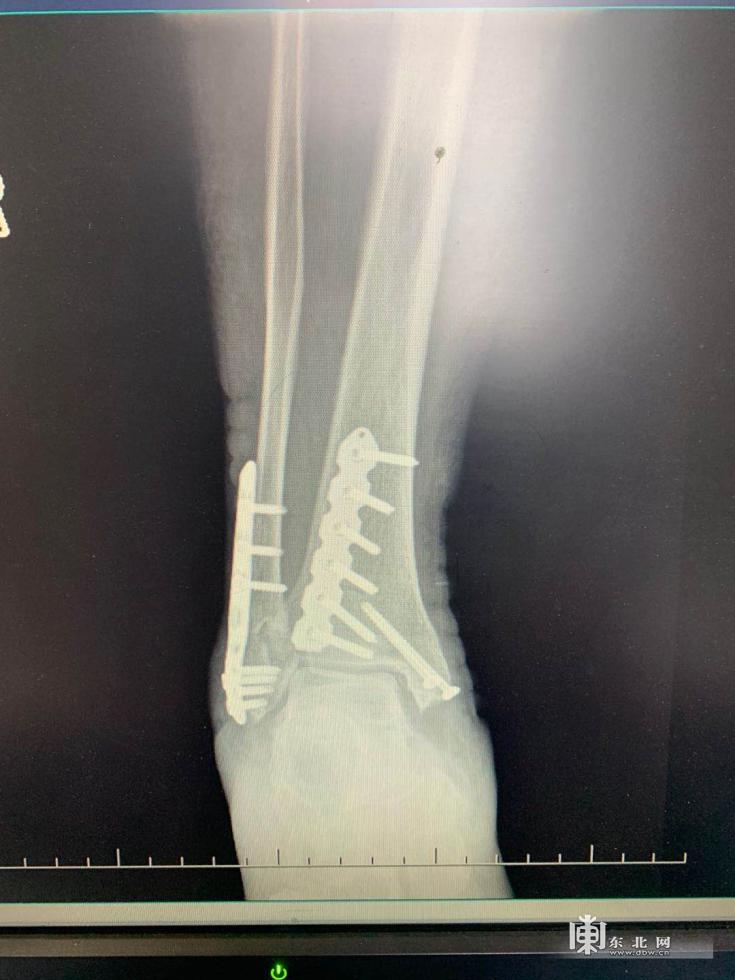

患者术后X射线图像

影像学检查结果显示,周女士为右侧足踝三踝粉碎性骨折,属于足踝骨折里的重度骨折,这个结果让周女士和家人都感觉到奇怪。只是崴到了脚踝,怎么一下子就骨折了呢?还是三踝骨折!

据哈尔滨市第五医院骨科五病区医生苏郁介绍,在日常门诊接诊时也会有多踝骨折的患者,但是像周女士这种三踝骨折的情况相对较少,而且是粉碎性骨折。根据苏郁了解周女士的既往病史和生活习惯并配合骨密度检查,周女士属于骨质疏松,正是因为骨质疏松才导致这次受伤如此严重。因为伤情严重,周女士想赶紧手术。但是苏郁医生表示手术还需要完善相关检查以及等待一个最佳的“时机”。苏郁表示,这里指的“时机”是指手术的最佳时间。因为踝关节周围的软组织比较薄,一旦受伤后软组织挫伤的情况比较重。所以在手术之前,要经过严格的消肿。如果肿胀不消除,术后感染的风险也比较高,特别是像这种复杂的多踝骨折。所以踝关节骨折手术时机的选择也比较重要。苏郁医生与骨科五病区白云星主任反复商讨手术方案,决定为其进行“右侧三踝粉碎性骨折切开复位内固定”。术中,医生们选择了从右踝内侧和后外侧进行切口,同时利用后外侧切口联合固定外踝和后踝,最大限度减少患者软组织损伤的程度,减少皮肤坏死的几率。术后周女士恢复良好,现已自行出院回家修养。